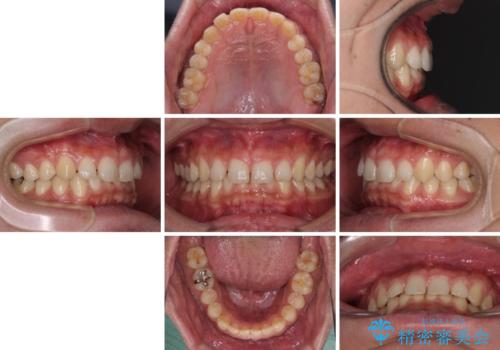

深い咬み合わせと隙間の空いた歯列をワイヤー矯正で改善

- 前歯の隙間と深い咬み合わせを改善したいとのことで来院された患者様です。

マウスピース矯正の自己管理が面倒とのことで、ワイヤー矯正により治療を行うこととしました。

奥歯の咬み合わせは理想的な状態であったため、ワイヤー矯正でもインビザラインでも比較的容易に対応可能でした。